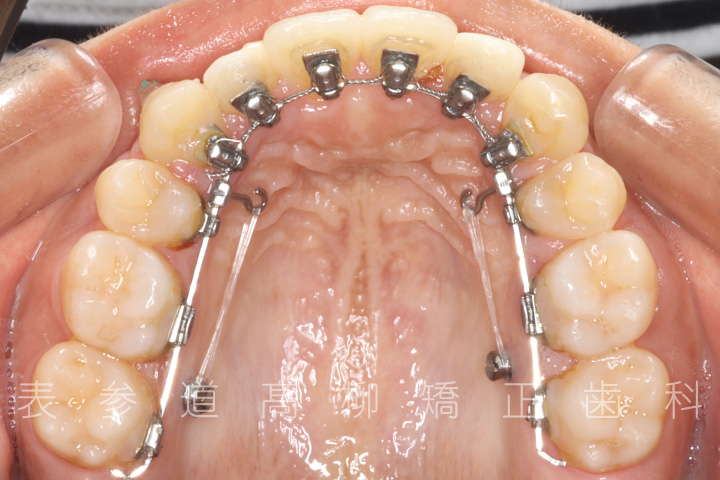

・歯科矯正用アンカースクリューを併用し、前歯部を後方へ移動する

・歯科矯正用アンカースクリュー

・上下歯列の緊密な咬合関係の確立に顎間ゴムを併用(装着時間20時間以上/日)